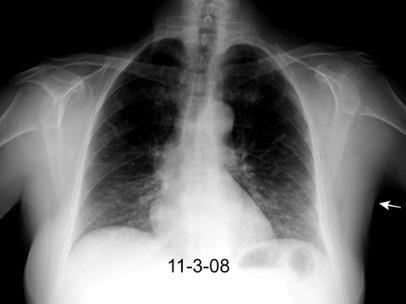

Asimetría de las partes blandas en Ca. de mama

Recidiva local Afectación de la piel